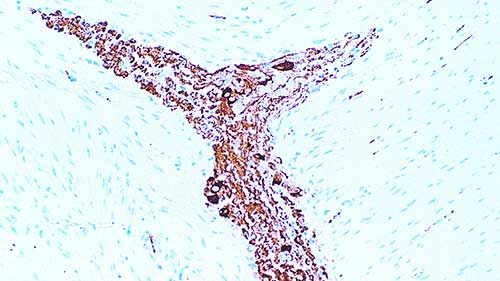

IHC-P analysis of human small intestine using GTX01921 nNOS antibody [NOS-125]. Note cytoplasmic staining of enteric ganglia.